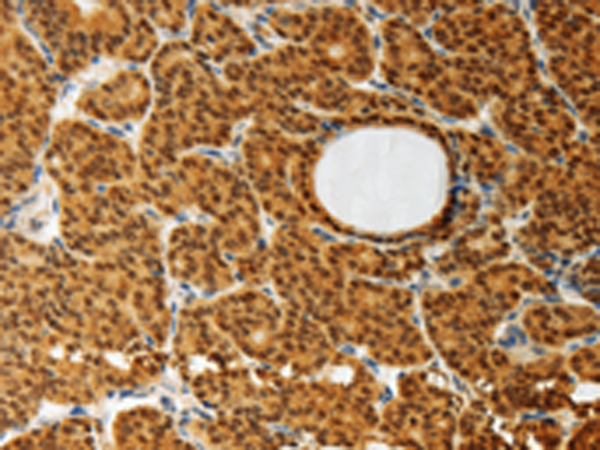

分类: 科研抗体货号: P11181别名: AMD; SAMDC; ADOMETDC应用: IHC反应种属: Human, Mouse, Rat